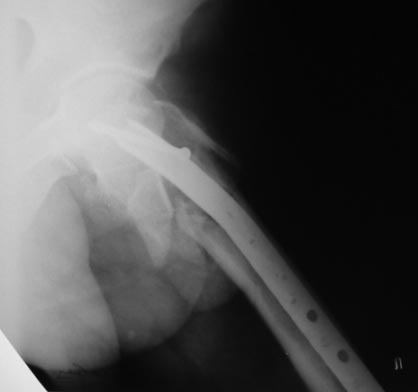

Вложение не в текстовом формате было извлечено…

Имя     : 4 бЛУИ?БМШОЩК 16.01.2013.jpg

Тип     : image/jpeg

Размер  : 24063 байтов

Описание: отсутствует

Url     : http://weborto.net:8080/pipermail/ortho/attachments/20130121/1122b3fc/attachment-0008.jpg